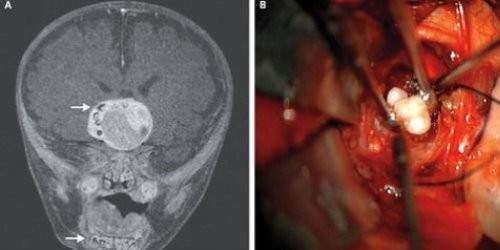

Un bebe de cuatro meses de Maryland podría ser la primera persona que ha tenido dientes formándose en el cerebro.

Como lo oye. Según reporta The Huffington Post, basado en un estudio publicado por el New England Journal of Medicine, el diente encontrado en el cerebro del niño se formó como resultado de un tipo específico de tumor raro. El diente ha sido removido y el infante está bien.

En este caso los doctores sospecharon que algo andaba mal cuando la cabeza de niño parecía estar creciendo a una velocidad mayor a la normal para los niños de su edad. Una radiografía del cerebro reveló el tumor que contenía estructuras similares a los dientes de la quijada inferior.

El niño fue operado y los cirujanos encontraron que en efecto el tumor tenia varios dientes completamente formados.